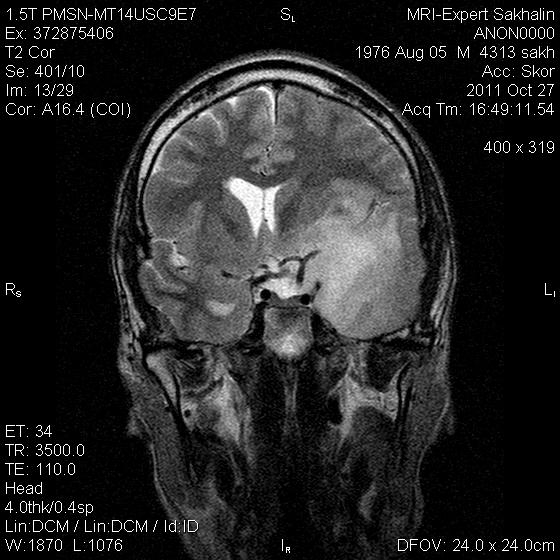

Помогите разобраться!Образование головного мозга.

Мужчина без направления.Жалобы на потерю памяти,шум в ушах в течение последнего года.

Заподозрила образование  из сосудистого сплетения заднего рога бокового желудочка  .Смещение срединных структур.Здесь отек смешанного типа?

опухоль с патологически расширенными сосудами в ее строме.

Вряд ли это из желудочка, височный рог (кажется) виден на одном из сканов, он не расширен. Скорее всего глиальная опухоль. А то, что выглядит как асширенные сосуды - скорее всего кистозные полости.

Вы правы, я затупила- смторела на  flaer , а думала о Т2 , конечно  же это никакие не сосуды , а кистозные полости.

Не характерный тип накопления при эпиндимоме (если подозреваете желудочек),  и тем более для сосудистой неоплазии, к тому же слишком большой мягкотканный компонент.

Отсутсвие накопления  позволяет предположить глиальную опухоль высокой степени дифференцировки.

Справедливости ради, нужно отметить необычность наблюдения, а именно эти преусловутые кисты. Что это за кисты, каков их патогенез? На аксиальных сканах выглядит как длинная тонкая исчерченность.  В результате некроза?  99% что нет. Похожи или на аксональную дегенерацию или сосуды. Я склоняюсь ко второму, быть может оборвавшийся неоангиогенез, слепо заканчивающиеся зачатки патологического сосудистого русла,  со сверхнизким кровотоком.  Хотя это не укладывается в высокодифференцированную опухоль.

Согласен с Евгением. Больше похожа на анапластическу глиому - астроцитому или олигодендроглиому. У глиобластомы, как правило, преобладает кистозный компонент.

Передумал, под аргументрованными высказываниями мудрых товарищей - глиома или астроцитома...